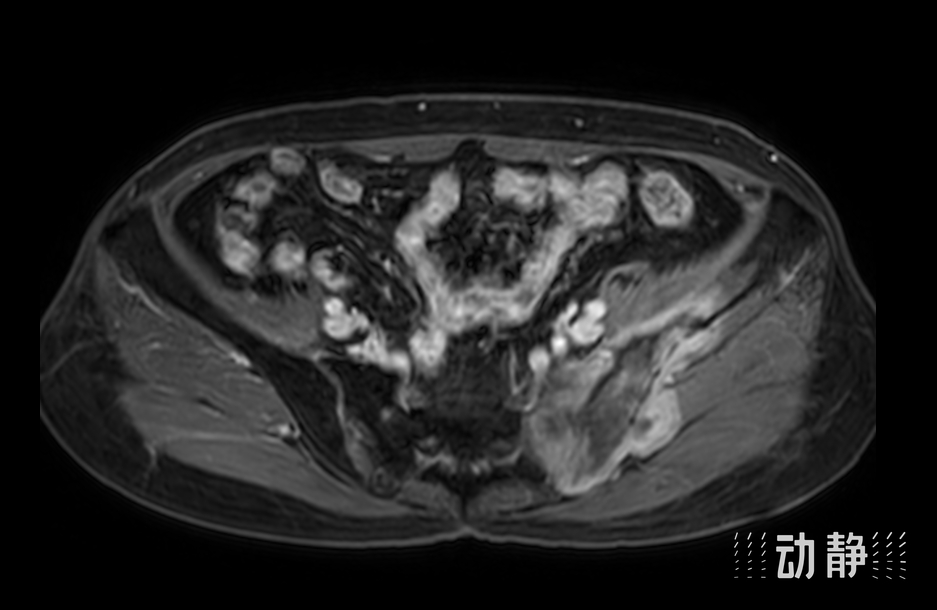

患者术前MR检查

患者术前MR检查

骨肉瘤是一种高度恶性的肿瘤,因其侵袭性强、发展迅速而备受医学界关注。王兰的肿瘤范围广泛,不仅累及左侧骨盆,还进一步侵犯了左侧骶骨。这一区域被视为手术禁区,因为其解剖结构异常复杂,涉及泌尿系统、消化系统、大血管、大神经等重要结构,手术难度极大,出血量往往高达上万毫升。